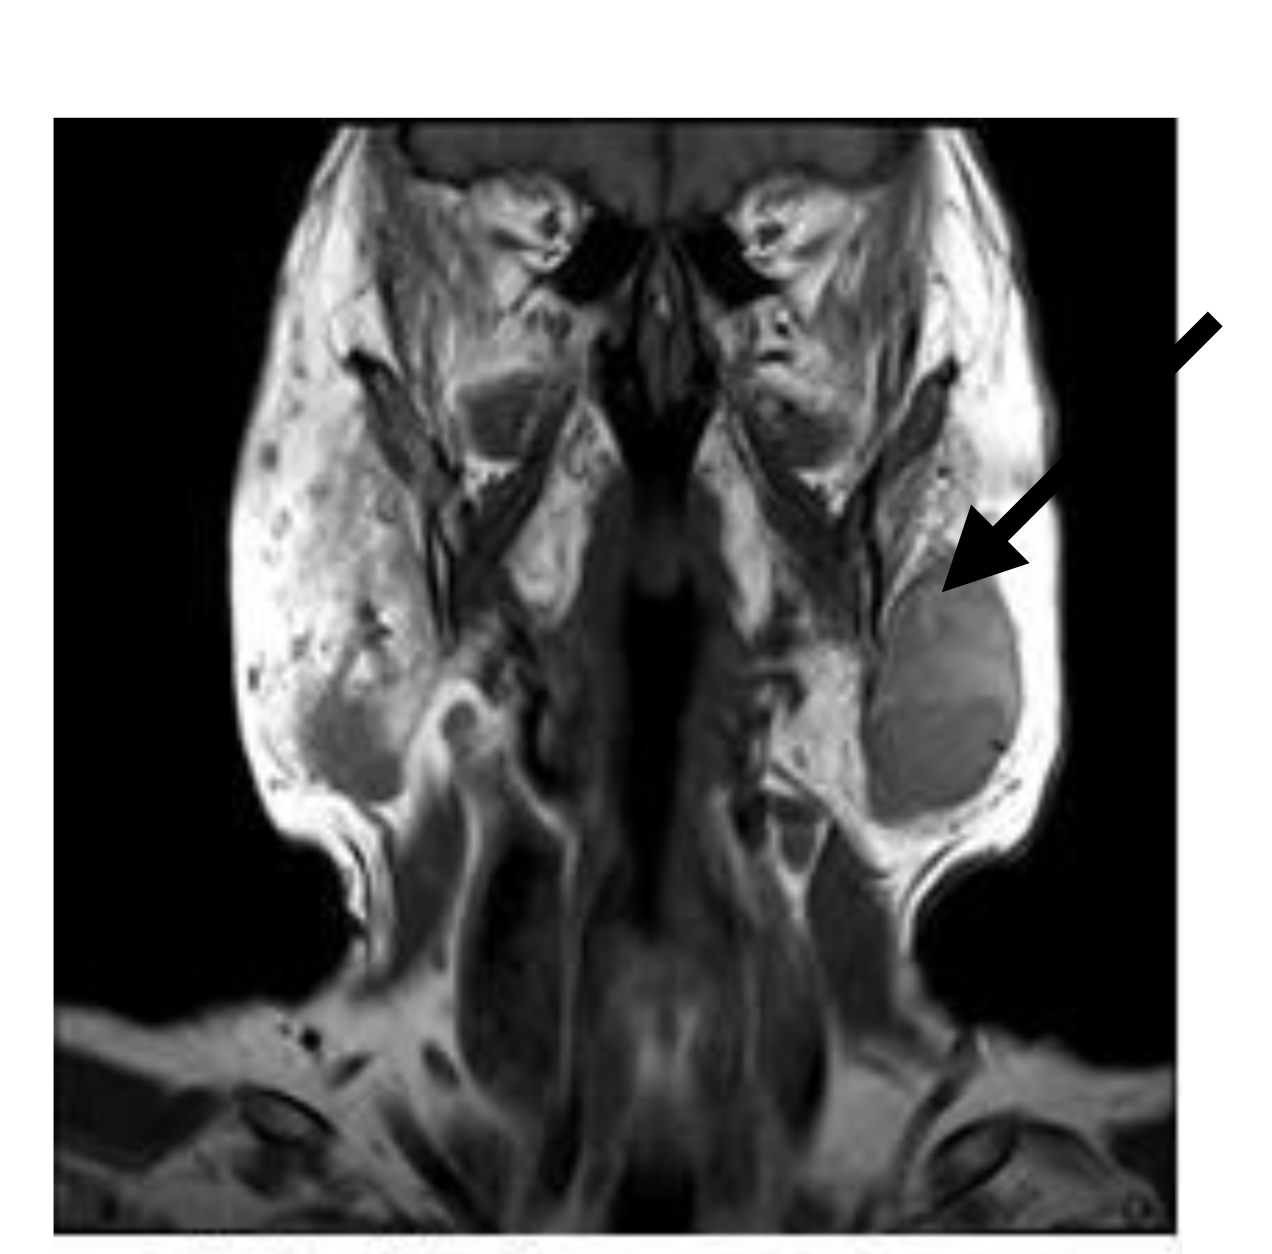

Q

MATCH to letters

1. Subscapularis muscle

2. Inferior labrum

3. Glenoid

4. Supraspinatus muscle

5. Clavicle

6. Superior labrum

20

A

A. clavicle

B. superior labrum

C. supraspinatus muscle

D. glenoid

E. inferior labrum

F. subscapularis muscle